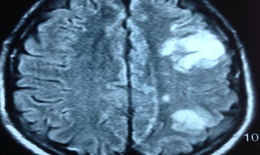

Ca mổ sáng 16/2/2017 là một bệnh nhân (BN) mắc u não rất sâu, BN rối loạn thăng bằng, u vùng bán cầu tiểu não và liên quan đến rất nhiều dây thần kinh sọ não. ThS.BS Nguyễn Đức Liên, Phụ trách Khoa Ngoại thần kinh cho biết: Các bác sĩ đã sử dụng nhiều trang thiết bị hiện đại trong phẫu thuật như kính hiển vi phẫu thuật, dùng các máy kích thích thần kinh để dò chức năng thần kinh nhằm bảo vệ các dây thần kinh của BN sau mổ. Ngoài ra còn có thiết bị rất hiện đại máy hút u  siêu âm làm giảm thiểu các động tác hút cơ học giảm các sang chấn cho người bệnh. Với trang thiết bị hiện đại và các chuyên gia có kinh nghiệm, ca mổ diễn ra khá suôn sẻ.

Trước đó, ngày 13/2, các bác sĩ cũng đã tiến hành phẫu thuật thành công cho BN Bùi Thị Phú, 54 tuổi, quê Hải Phòng bị bệnh u màng não ở vùng vận động. BN nhập viện trong tình trạng trí nhớ kém, liệt tay, chân yếu không đi lại được, kích thước khối u lớn khoảng 7cm nằm ở vùng vận động, vùng ngôn ngữ. Các bác sĩ đã sử dụng kỹ thuật mổ dưới kính hiển vi hiện đại, dùng hệ thống thần kinh dẫn đường để xác định cấu trúc não quan trọng và vùng ranh giới nguy hiểm. Sau 4 ngày, tình trạng BN cải thiện, BN ngồi dậy được, tay cử động khỏe hơn, trí nhớ tốt, nhận biết và nói chuyện bình thường. Hiện BN đang được các bác sĩ hướng dẫn tập thay đổi tư thế, tập đi, tập các cơ phục hồi chức năng.

Một trường hợp khác, BN Trần Trung H, 9 tuổi, mổ u vùng giao thị giác – một trong những loại u khó nhất, là thách thức với các phẫu thuật viên và bác sĩ điều trị. Kết quả sinh thiết khối u cho thấy đây là u lành tính nhưng khối u đã chèn ép gây giãn não thất, trong khi chức năng thị lực còn tốt. Đây là ca bệnh khó đòi hỏi phải cân nhắc giữa biện pháp mổ lấy u, điều trị gamma knife, hay là điều trị hóa chất…?. Sau khi hội chẩn với các bác sĩ trong BV và đoàn chuyên gia Mỹ, các bác sĩ xác định đây là u lành, diễn biến chậm, thị lực còn tốt nên đã quyết định điều trị tình trạng giãn não thất trước, sau đó chụp lại theo dõi tiếp sự phát triển và cho hướng điều trị tốt hơn.